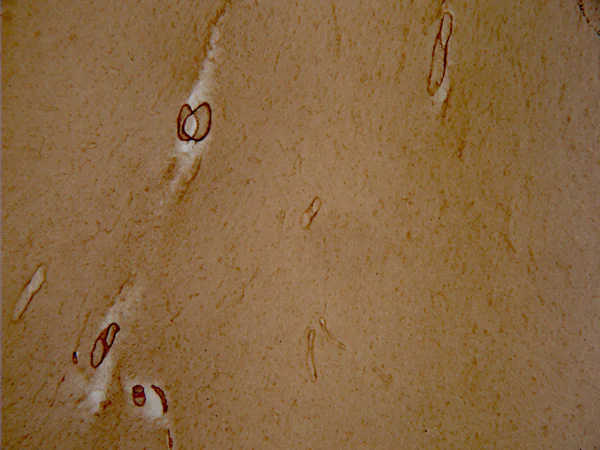

Immunohistochemistry - Free Floating - Anti-vascular Amyloid 1-42 antibody [mOC31] - Conformation-Specific (AB201059)

Immunohistochemical staining of human brain tissue from a patient with a diagnosis of Alzheimers disease male 81 years 5 hour post mortem index tangle stage 5 plaque stage B mini mental status exam score 12. Sections were cut using a vibratome. No antigen retrieval was performed. Free floating sections were stained using using ab201059 at a dilution of 50 ng/mL. The secondary antibody used was a biotinylated goat anti-rabbit at a dilution of 1/225 which was blocked with normal goat serum. The sample was visualized using ABC solution (1 hour incubation) followed by 1-4 minutes of DAB. The sample was mounted and allowed to dry overnight followed by dehydration in increasingly concentrated ethanol solutions.

Image courtesy of Professor Charles Glabe, UC Irvine